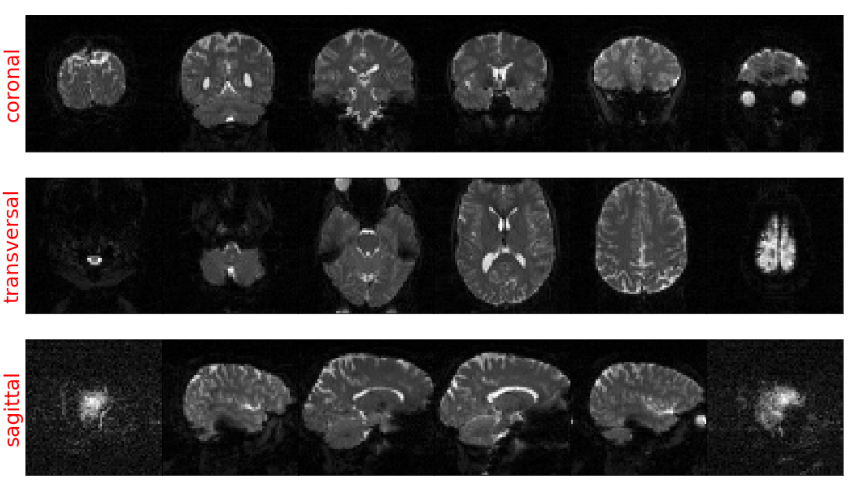

接着就可以通过Matplotlib可视化展示数据了,因为组成这些数据的是体素,是三维的图像,我们无法直接看到所有的数据,所有进行切片操作,通常会横切大脑从而获得冠状面(coronal)、横切面(transversal)和矢状面(sagittal)这3个平面,理解这三个概念很重要,如下图:

- 冠状面为左,右方向将人体纵切为前后两部分的断面

- 横切面指横向水平切割的平面

- 矢状面是指将躯体纵断为左右两部分的解剖平面

这就是通过sMRI数据绘制出的大脑结构图了,其中第0层切片是最低的一个(接近脖子位置),而第50层切片是最高的一个(接近头顶),在第20层,可以看具有眼睛的切片。